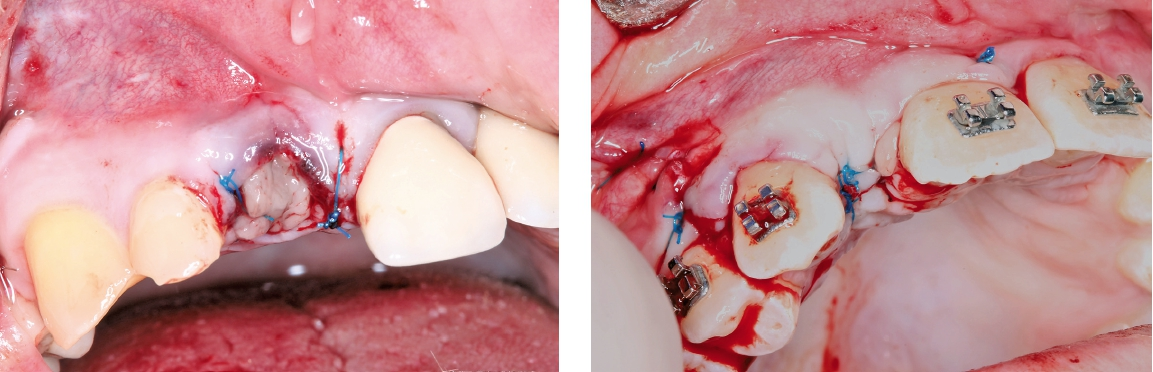

Letztendlich bestand aus kieferorthopädischer Sicht keine Kontraindikation für eine unverzügliche chirurgische Intervention mit nachfolgender implantatprothetischer Versorgung bei derart fortgeschrittener horizontaler Atrophie in regio 12 und 22 (2,5 mm mit großer Konkavität). Insofern wurde nach erneuter intensiver dokumentierter Beratung und Aufklärung wie auch wirtschaftlicher Aufklärung nach entsprechender beidseitiger Leitungsanästhesie am Foramen infraorbitale und zusätzliche intraoralen und vestibulären Infiltrationsanästhesien zunächst ein breiter Mukoperiostlappen von regio 14 bis 24 gebildet (Abb. 4) und zur Förderung der Durchblutung des allogenen Transplantates wurden entsprechende Bleeding-Points (entsprechende Perforation der bukkalen Kortikalis) gesetzt (Abb. 5). Die mit Hilfe von CAD/CAM durch das Labor ProDent (Zahntechnikermeister Thomas Blaschke) hergestellten kortikospongiösen Blöcke nach DVT-Auswertung wurden mit entsprechenden Osteosyntheseschrauben fixiert (Abb. 6) und mögliche Restspalträume mit allogener Spongiosa abgedichtet und lateral auskonturiert.

Die nach der Technik von Choukroun et al. (A-PRFTM) hergestellten Fibrinmembrane wurden oberhalb der Augmentate regio 12 und 22 als autologe Fibrinmembran platziert und die Wunde nach entsprechender Split-Flap-Technik und nach entsprechender Periostschlitzung speichel- und wunddicht vernäht (Abb. 7). Direkt postoperativ wurde die Patientin mit Amoxicillin 1000 mg 2 x1 täglich wie auch Arilin 500 mg 3×1 täglich antibiotisch abgeschirmt zur Verhinderung einer aeroben/ anaeroben postoperativen Infektion. Die Wundheilung verlief komplikationslos. Die Nähte konnten nach 10 Tagen entfernt werden (Abb. 8).